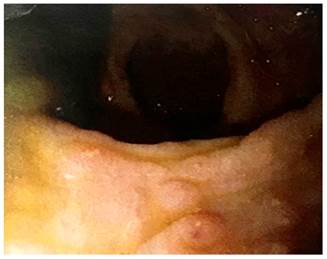

This is the case of a 15-year-old patient without any significant history of disease who was referred to our hospital due to hematochezia. In addition, he had the following family history: type 2 diabetes (mother), scleroderma (maternal aunt), amyloidosis (maternal aunt), and gastric cancer (great-grandmother). According to the patient, he was 7 years at the time of disease onset, experiencing hematochezia and mild abdominal pain that improved after defecation. In 2011, he underwent a colonoscopy in which 3 to 4 mm raised pseudopolypoid lesions were observed in the sigmoid colon and rectum and malakoplakia was described in the biopsy report. At that time, he was treated with oral ciprofloxacin 500 mg for 14 days, experiencing an improvement of his symptoms. In 2016, another colonoscopy was performed due to proctorrhagia and mild abdominal pain. Again, nodular pseudopolypoid lesions were identified in the sigmoid colon and the rectum (Figure 1), and inflammatory polyps with aggravation foci, numerous histiocytes and reactive epithelial changes were described in the biopsy report. On this occasion, he was administered oral ciprofloxacin 500 mg every 12 hours for 14 days, experiencing symptomatology improvement. In July 2018, irregularly distributed pseudopolypoid lesions with normal colonic mucosa and flat areas of pearly appearance with irregular borders were observed on a new colonoscopy (Figure 2); in addition, the following findings were described in the biopsy report: inflammatory polyps, chronic colitis accentuated with periodic acid Schiff (PAS) staining, and absence of Michaelis-Gutmann bodies.

Figure 1 Videocolonoscopy showing nodular pseudopolypoid lesions on the mucosa of the sigmoid colon and the rectum.